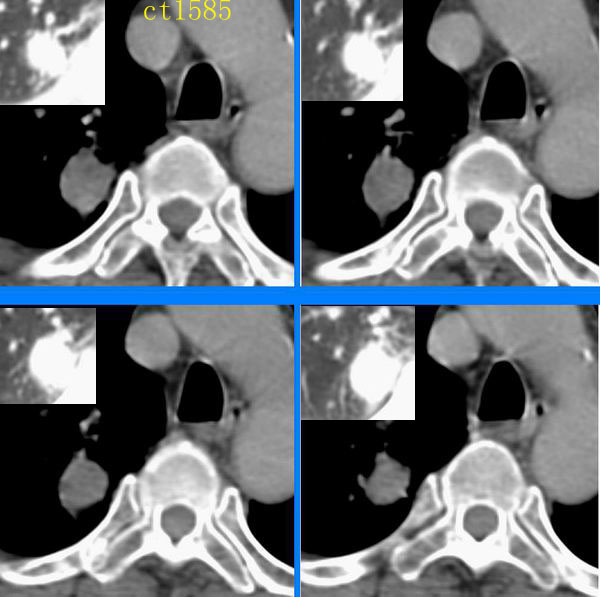

ct1585:liuwensi 提供

m,64y,体检发现右肺上叶后段孤立性结节,纵隔内未见肿大淋巴结影右肺病理是结核球